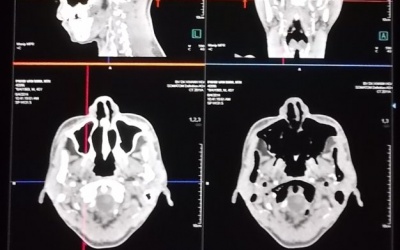

Anh Nguyễn H., 29 tuổi, ở huyện Kinh Môn, tỉnh Hải Dương bị cán gương chiếu hậu ô tô tải đâm xuyên vào hốc mắt bên phải do anh H vừa điều khiển xe máy vừa cầm ô che mưa, lại không đội...